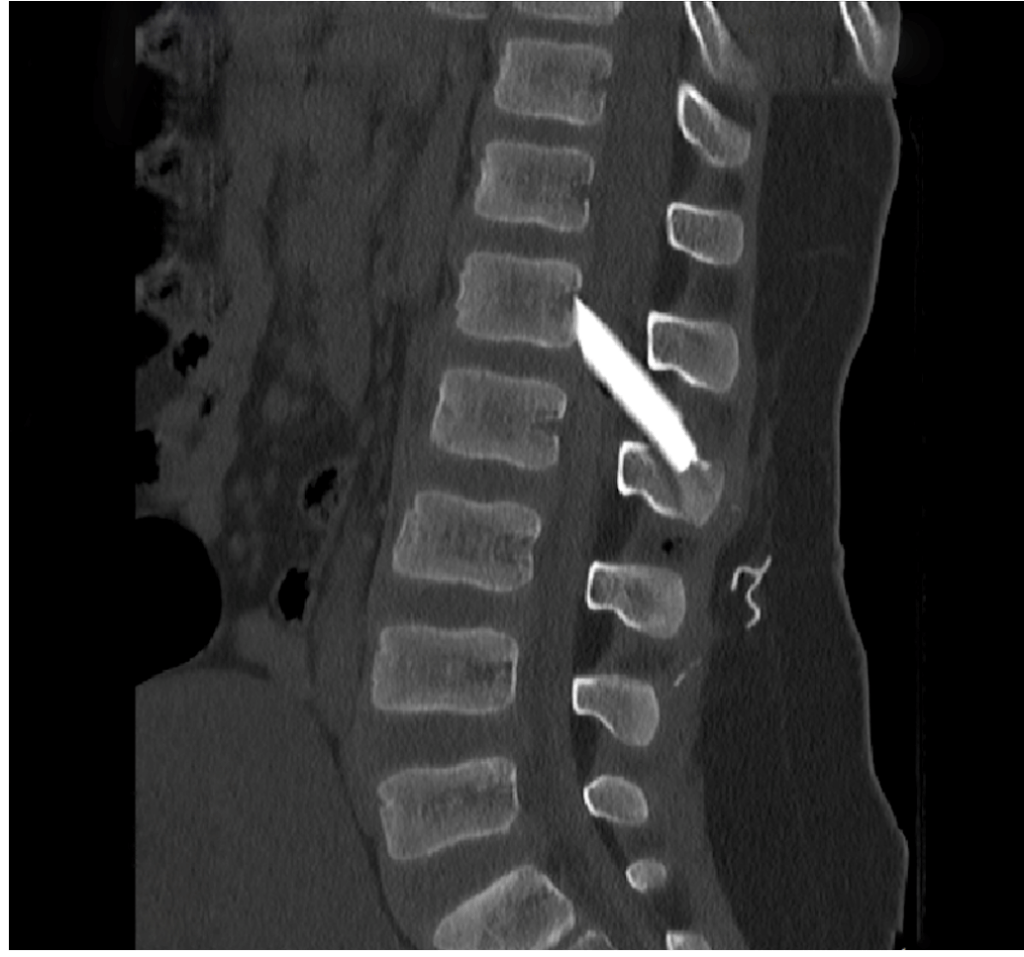

Οι μαγνητικές και αξονικές τομογραφίες πραγματοποιήθηκαν άμεσα, επιβεβαιώνοντας τις αρχικές υποψίες: δύο μεγάλα κομμάτια γυαλιού είχαν ενσφηνωθεί στη σπονδυλική στήλη, εισχωρώντας εντός του σπονδυλικού σωλήνα σχίζοντας την ιππουρίδα και την μήνιγγα που την περιβάλλει.

Ακολούθησε άμεση εισαγωγή του παιδιού στο χειρουργείο, όπου με πολύ προσεκτικούς χειρισμούς και τη χρήση προηγμένου εξοπλισμού, όπως το σύστημα χειρουργικής πλοήγησης, πραγματοποιήθηκε επιτυχής αφαίρεση όλων των κομματιών γυαλιού μετά από ένα πολύωρο και απαιτητικό χειρουργείο.